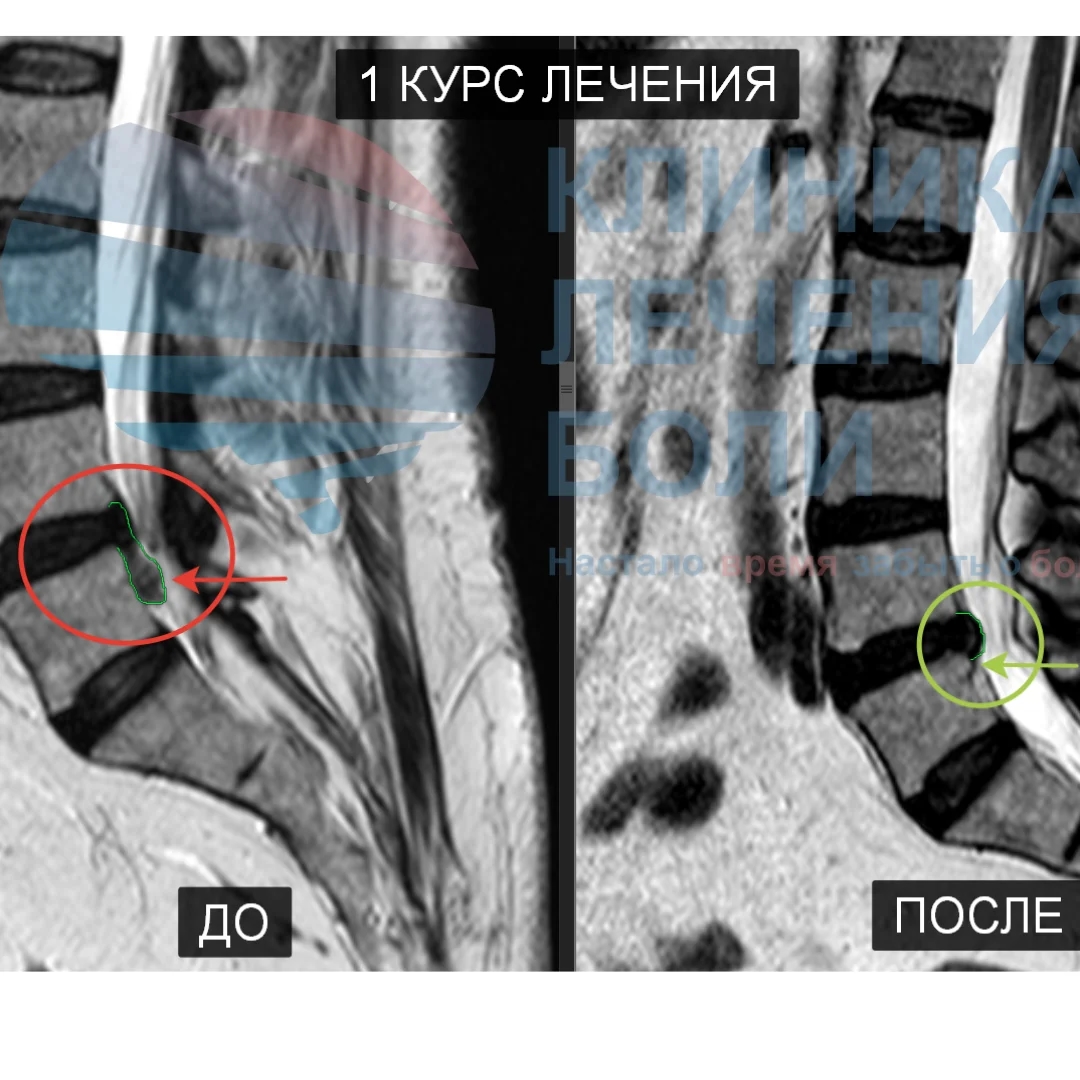

Повышаем вероятность уменьшения или исчезновения грыжи до 94% с помощью метода модулируемой резорбции

По статистическим результатам разница в скорости восстановления при Спонтанной и Модулируемой резорбции составляет от 5 до 10 месяцев. Метод достоверно уменьшает сроки нетрудоспособности, позволяет быстро купировать болевой синдром, увеличить подвижность и быстрее вернуться к рабочему графику.

Мы первый в Тюменской области центр, который занимается резорбцией грыжи диска (методом безоперационного уменьшение или полного рассасывание грыжи). Благодаря нашему правильному подходу сотни пациентов избежали операций по удалению грыжи диска.